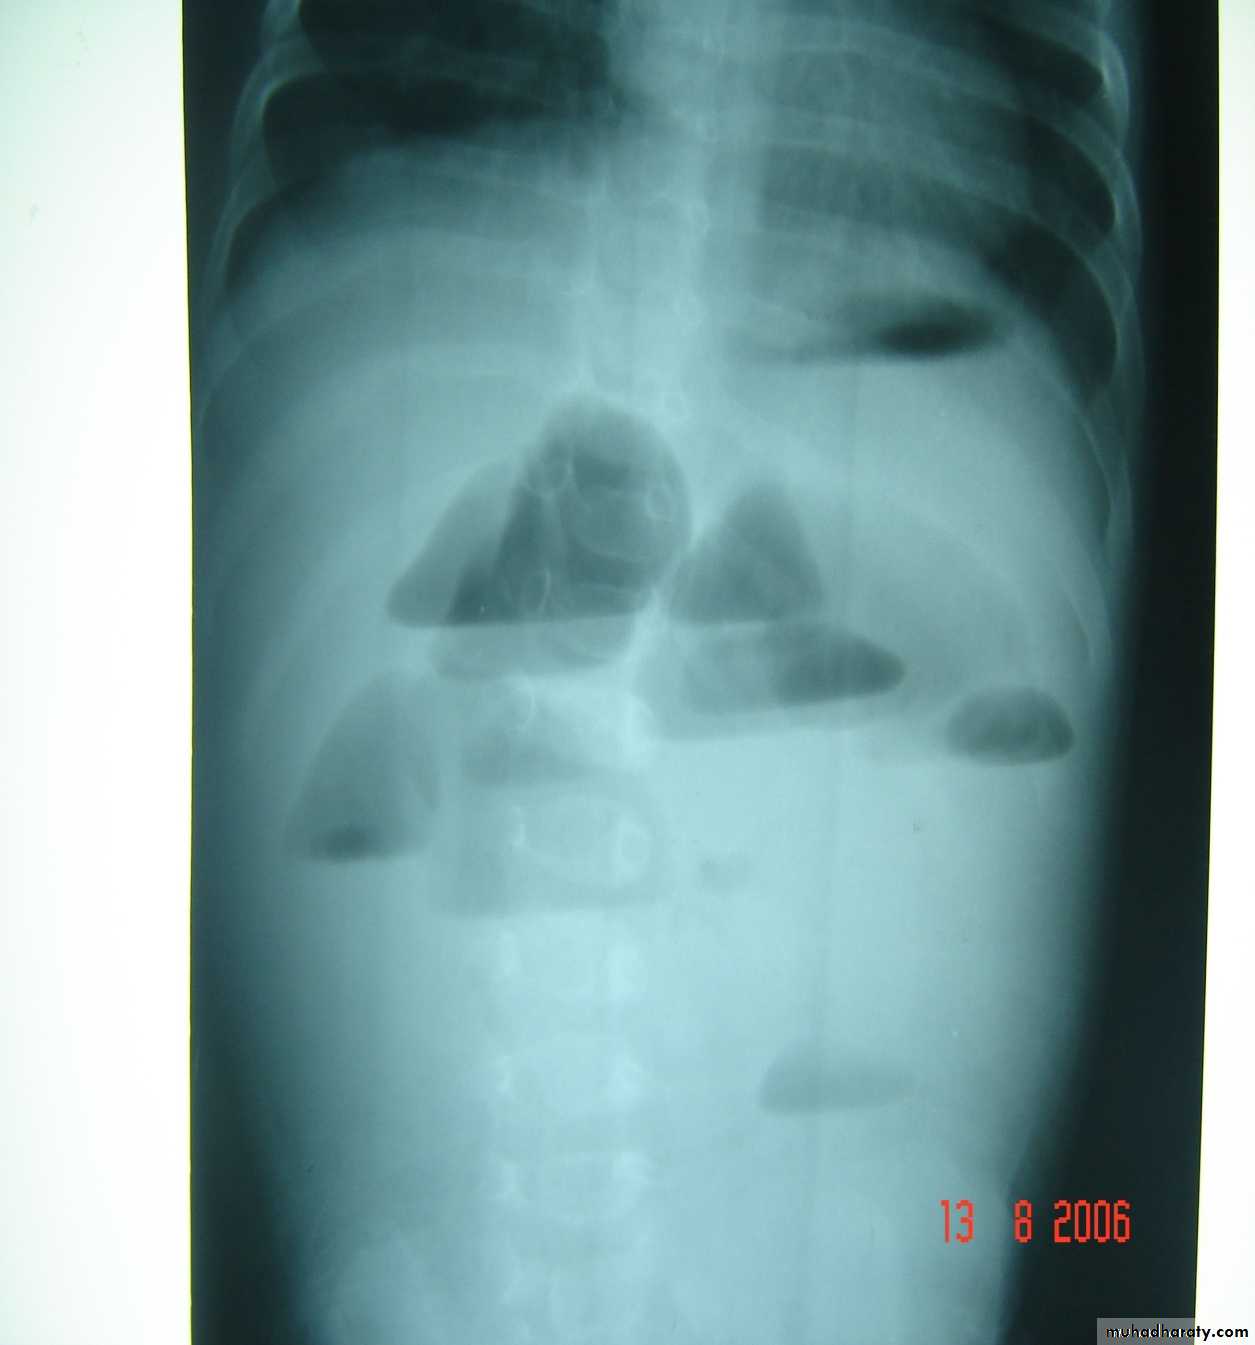

Bowel Obstruction

first photo upper bowel obstruction // second photo lower bowel obstructionDescription:

double bubble signCauses of obstruction in the first photo:

1- duodenal obstruction2- duodenal atresia

3- annular pancreas

4- mal-rotaion of bowel

Cardinal symptoms of bowel obstruction (first photo):

1- mild abdominal distention (epigastric distention)2- failure if pass of meconium

3- bile stain vomiting